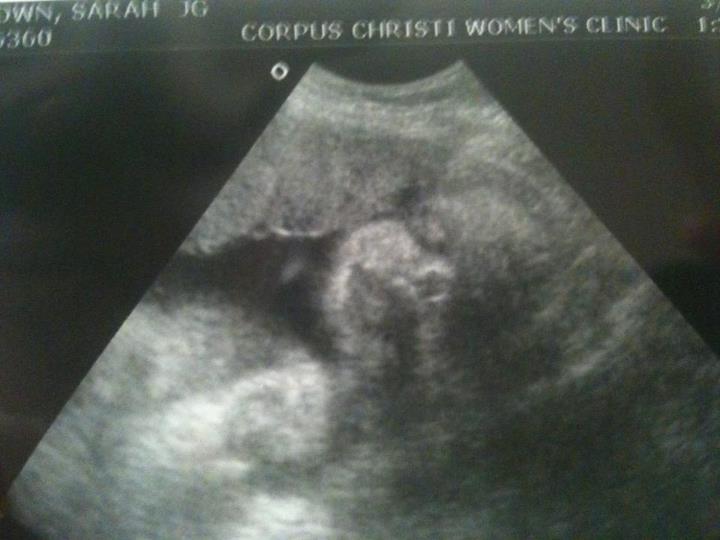

I am preparing to go on unpaid maternity leave for the birth of Lil' A$$kicker 3.0, who is due May 12. We are a little nervous about our regular expenses: Rent, groceries, etc... plus the medical bills and new baby expenses. I wanted to give those who have reached out and offered to help a place to do so.